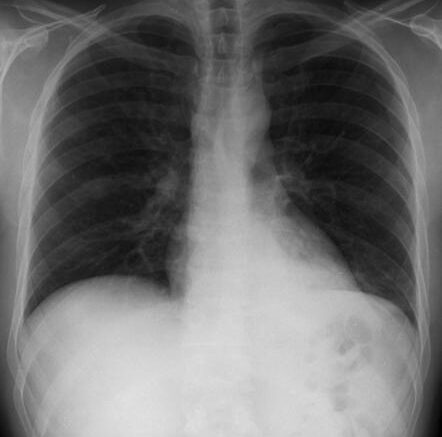

Η πνευμονία είναι η οξεία φλεγμονή του πνεύμονα. Διακρίνουμε τη νοσοκομειακή πνευμονία και την πνευμονία της κοινότητας. Βήχας, πυρετός, πτύελα είναι συνήθη συμπτώματα. Σε αρκετά άτομα (κυρίως ηλικιωμένα, άτομα με ανοσοκαταστολή), ο βήχας, ο πυρετός και τα πτύελα μπορεί να απουσιάζουν. Δύσπνοια, ναυτία, έμετος, διάρροια, εφίδρωση, ρίγος, βάρος στον θώρακα, ενδέχεται να εμφανιστούν. Επιπλοκές είναι η αιματογενής διασπορά, η πλευρίτιδα, το εμπύημα, η καρδιολογική απορρύθμιση.